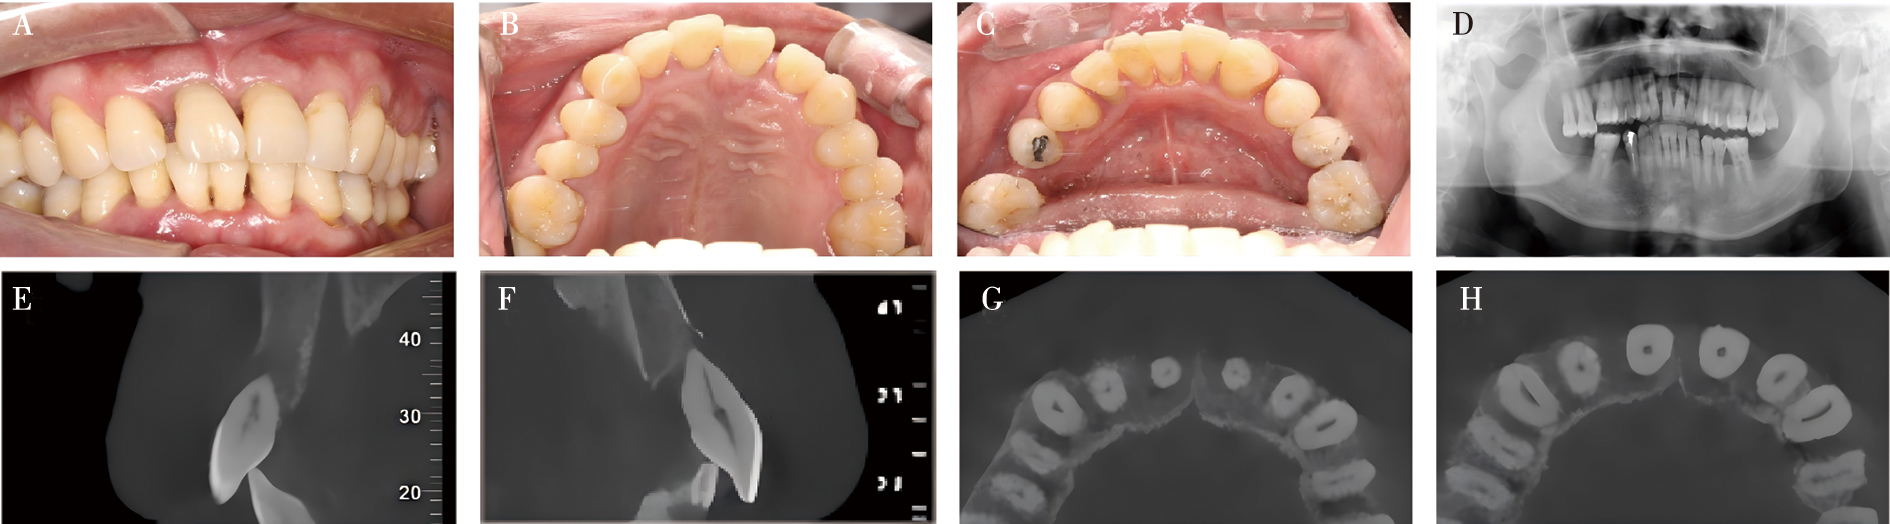

Zhang CR, Liu Q, Yang JW, et al. A digital technique for splinting periodontally compromised mobile teeth in the mandibular anterior region[J]. J Prosthet Dent, 2021, 125(4): 560-563.

Liu YC, Bai SZ, Zhong S, et al. Digital workflow for periodontal splinting with a guided device[J]. J Esthet Restor Dent, 2023, 35(4): 621-624.